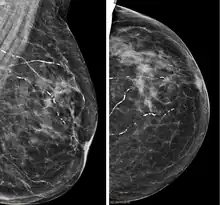

Right breast mammograms showing several calcified arterioles. Patient 94 years old.